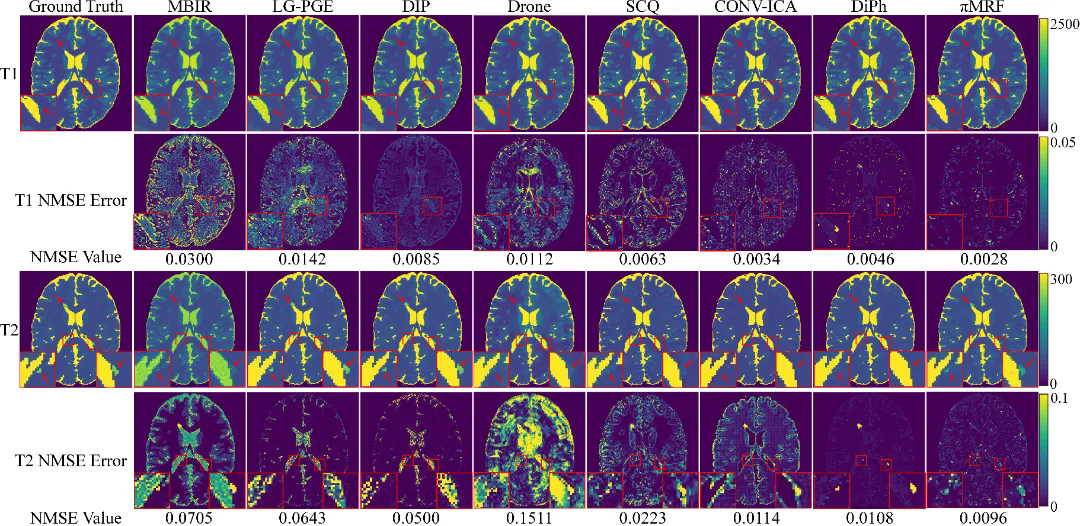

在数字仿真、水模仿体以及在体人脑实验中,πMRF在极端欠采样条件下均表现出更高的定量准确性与空间一致性,能够稳定恢复T1、T2和PD参数分布,并在组织边界及病灶区域保持更可靠的细节表达,整体性能显著优于现有对比方法。上述结果表明,该研究有效缓解了 MRF 在极端欠采样条件下面临的不适定逆问题,展示了“物理模型与连续神经表示深度融合”在复杂医学成像反演任务中的应用潜力。

图5:在体人脑实验结果